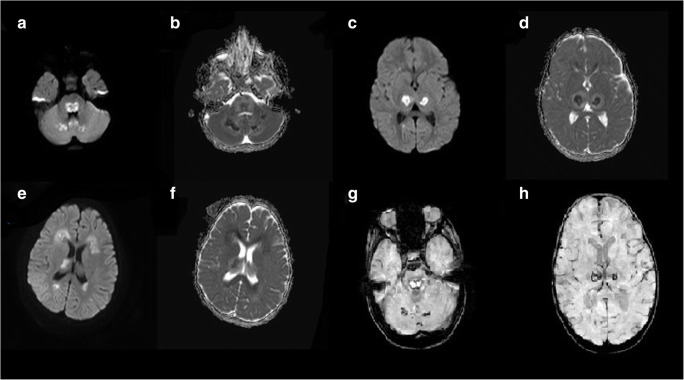

Fig. 2.

Diffusion restriction consistent with cytotoxic edema was present on the diffusion MRI examination performed 4 days after the patient’s admission to the hospital. High signal intensities on DW images and low signal intensities on ADC maps were present in (a, b); bilateral cerebellar white matter, center and dorsal surface of the pons, and bilateral thalami (c, d); bilateral frontal and occipital periventricular white matter (e, f) suggesting ANE. The appearance of focal hemorrhagic signals of ANE in bilateral cerebellar white matter (g) and bilateral thalami (h) on SWI images